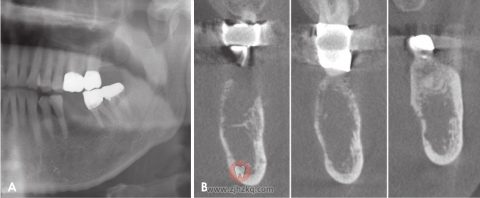

图2.A.全景片局部影像显示左侧下颌磨牙的根尖周放射可透性。B.全景片影像显示拔牙后约4个月植入种植体。

图3.A.全景片显示从左下前磨牙到第二磨牙有不清楚的渗透性骨质破坏。与图2A相比,病变已扩展至下颌管。B.根尖片可见浸润性骨质破坏和增大的软组织阴影(箭头)。

图4.A.矢状面锥束计算机断层扫描(CBCT)显示左侧下颌体溶骨性破坏和下颌管皮质缺失。B.横断面CBCT图像显示颊侧和舌侧皮质板部分穿孔和侵蚀。